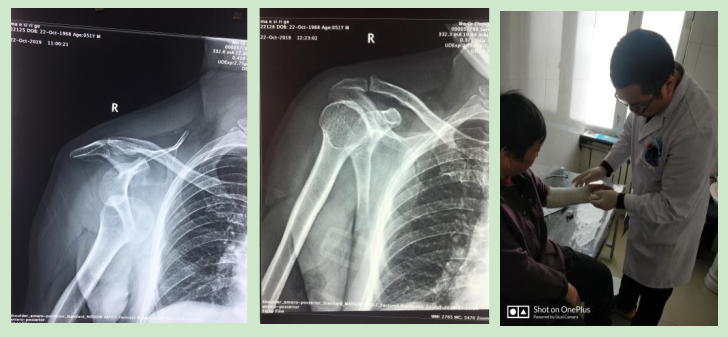

手法整复桡骨远端骨折、踝关节骨折、尺骨骨折、掌骨骨折、指骨骨折、跖骨骨折及肩关节脱位、桡骨小头半脱位等各类骨折脱位十余例,行小夹板固定及石膏托外固定十余例。